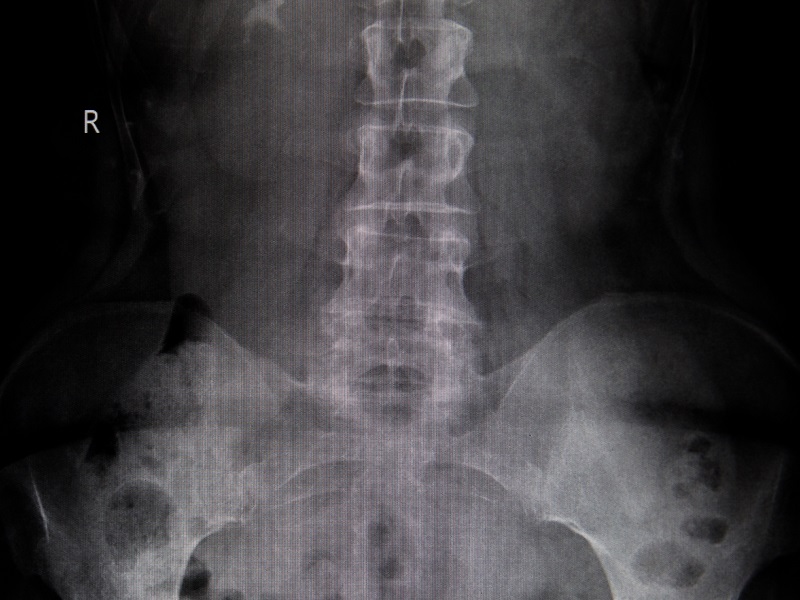

КТ хребта — це інформативний, сучасний метод візуалізації кісткових структур, хребців та хребетного каналу, міжхребцевих дисків та зв’язок. Завдяки цьому виду діагностики лікарі можуть поставити точний діагноз, відстежити морфологічні зміни та призначити ефективне лікування.

Комп’ютерна томографія дає лікарю детальну інформацію про кістки, хрящі, прилеглі судини й навколохребцеві м’язи, нервові закінчення.

КТ попереково-крижового відділу хребта покаже:

- защемлення нервових закінчень;

- дефекти будови хребта;

- грижі дисків;

- остеохондроз;

- просвіт хребтового каналу;

- зміни нервових відростків;

- переломи, гематоми, запальні процеси;

- дегенеративні зміни;

- наявність онкології, патології судин (із контрастом).